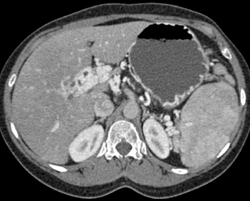

Diagnosis

Internal Carotid Aa Stenosis